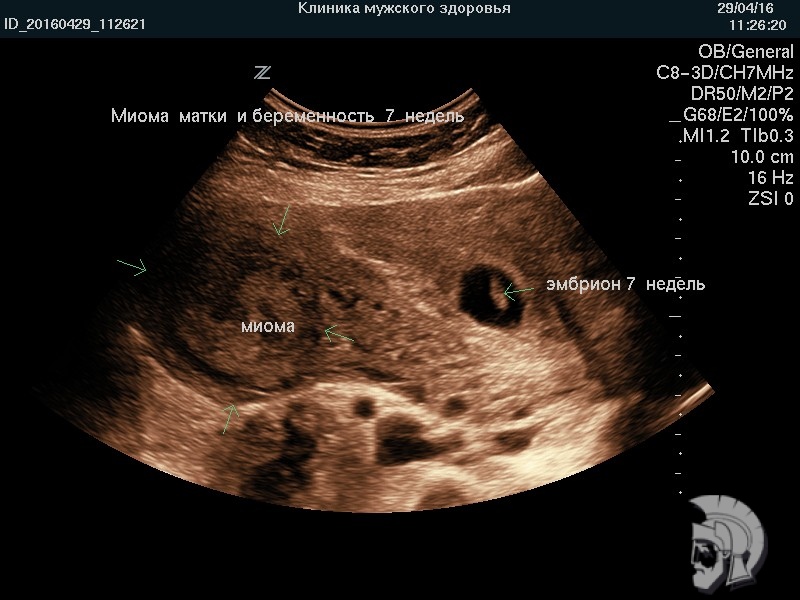

| Фото миомы матки и беременности 7 недель |

| Фото миомы матки. Крупный интерстициальный (межмышечный) узел в дне матки, деформирующий контур задней стенки |